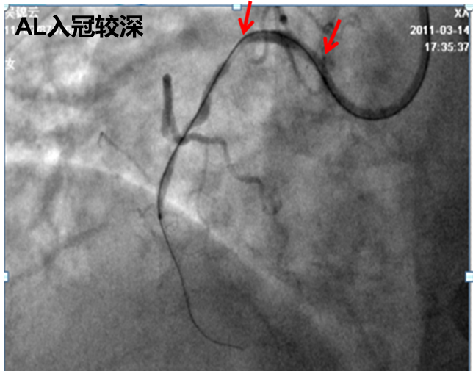

A. 患者右冠状动脉迂曲明显伴钙化,考虑手术过程中指引导管需要提供一定支撑力,选择了SAL0.75,必要时联合应用延长导管;

由于经桡动脉鞘管为6F,右冠状动脉近中段可见明显扭曲钙化,预估器械推送阻力较大且术式相对复杂,而右冠状动脉远段分叉病变处理需要指引导管提供一定支撑力,因此选用6F SAL 0.75指引导管。端头SAL 0.75较长头SAL 1.0发生嵌顿风险较低,开口发生夹层并发症也较低,安全性相对较高。